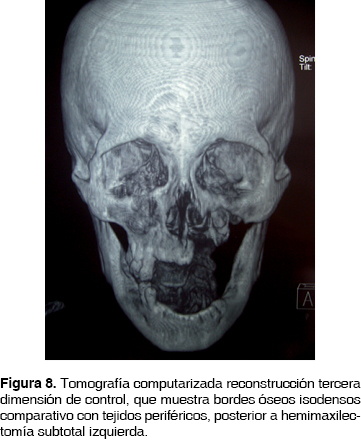

Se envía la pieza quirúrgica a patólogo oral reportando osteomielitis crónica maxilar con bordes libres de lesión. Continúa ambulatoriamente tratamiento farmacológico con penicilina G procaínica 800,000 UI cada 12 h por 30 días. Actualmente a 8 meses sin datos de recidiva (Figura 8).